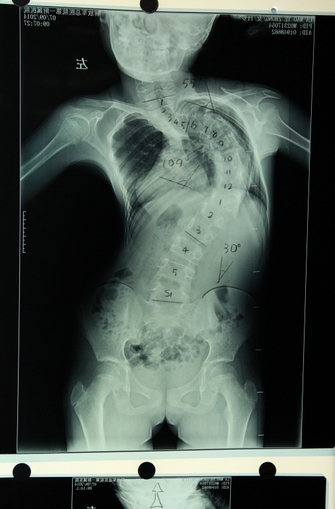

拉毛叶忠3岁时发现有脊柱侧后凸畸形,由于从小失去父母,无钱医治,一直没有治疗,侧凸畸形已超过120度,同时伴有105度的后凸畸形。近年来,由于脊柱畸形越来越严重,已经13岁的拉毛叶忠身高仅有110厘米,比同龄孩子要矮小很多。不仅严重影响正常发育和生活,而且多脏器受到挤压,经常疼痛难忍,呼吸功能受到严重损害。7月7日,由青海塔尔寺阿卡更登彭措带着到解放军总医院第一附属医院求治。

拉毛叶忠手术示意图

藏族孤儿拉毛叶忠患脊柱后突畸形严重影响正常发育

拉毛叶忠严重变形的脊柱